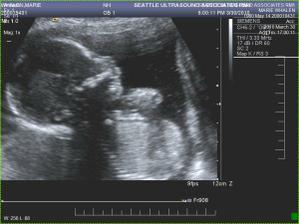

• 12.2.2010 Nas druhy ultrazvuk v 11. tydnu nam ukazal velmi aktivni miminko hybajici ruckama a nozkama.